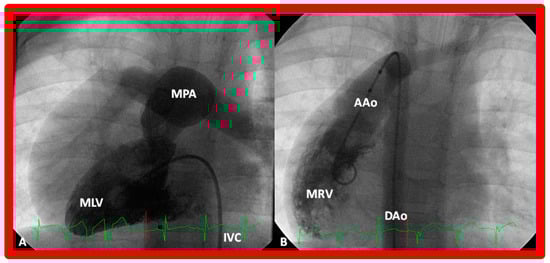

In theory, patients with cardiac malposition may have one (single) or two ventricles. The distinction between one and two ventricles is feasible by echocardiography (Figure 30) and angiography (Figure 31 and Figure 32).

Figure 36. (A) Cine frame from morphologic left ventricular (MLV) cineangiogram in a posteroanterior view of an infant with dextrocardia, exhibiting fine trabeculations of the MLV on the left side. The MLV gives origin to the main pulmonary artery (MPA), which is dilated. The position of the catheter in the inferior vena cava (IVC) is on the left side of the spine. (B) Demonstrates a morphologic right ventricle (MRV) in a posteroanterior view in the infant shown in (A); coarse trabeculations are seen. The right-sided MRV gives rise to the aorta, denoted by AAo. The aorta descends on the right side of the spine. The aortic valve is situated rightward and superior to the pulmonary valve. It is located anteriorly in the lateral view (not shown). This information suggests a d-loop of the ventricles and d-transposition of the great arteries in a subject with dextrocardia, a disorder suggestive of corrected transposition physiology. DAo, descending aorta. Replicated from reference [36].

Atrioventricular Valve-to-Semilunar Valve Relationship

It has been established that AV valves go with the respective ventricular chambers in that the mitral valve is an essential part of the LV while the tricuspid valve is an integral part of the RV [10,11,13,28]. The morphologic LV has little or no conus musculature, and consequently, the mitral valve and aortic valve are in fibrous continuousness with each other (Figure 35A,B, Figure 36A and Figure 37A,B). However, in the morphologic RV, a muscular structure (crista supraventricularis) separates the tricuspid valve from the pulmonary valve, and therefore, fibrous continuity between the AV valve and semilunar valve (Figure 31A, Figure 35C,D, Figure 36B and Figure 37C) cannot be demonstrated. These features may be demonstrated in echocardiography (Figure 37) and angiography (Figure 31, Figure 35 and Figure 36).